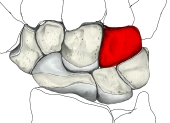

有鈎骨(手) (ゆうこうこつ、英:hamate)

・有頭骨は手根骨の1つで、遠位手根骨の中で最も内側(小指側)に位置する。

・イラストや写真を掲載しているサイトⅠ(左手・手背面のCG) ・イラストや写真を掲載しているサイトⅡ(2方向からの単体のイラスト) ・イラストや写真を掲載しているサイトⅢ(筋の付着が分かるイラスト) ・イラストや写真を掲載しているサイトⅣ(手根骨周辺の断面、赤は有頭骨) ・イラストや写真を掲載しているサイトⅤ(レントゲン画像、手根骨周辺) ・イラストや写真を掲載しているサイトⅥ(レントゲン画像、前腕下部~中手骨)